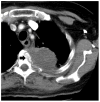

Methods: The single-arm prospective trial included patients with a single painful bone metastasis with unremitting pain with a score >50 on a pain scale of 0-100. Percutaneous computed tomography-guided RFA of the bone metastasis to temperatures >60 degrees C was performed. Endpoints were the toxicity and pain effects of RFA before and at 2 weeks, 1 month, and 3 months after RFA.